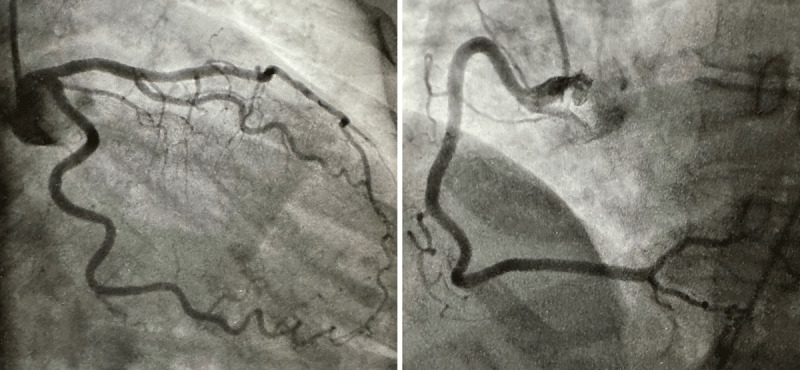

This Points to Remember column discusses the differential diagnosis of acute myocardial infarction with normal coronary arteries, one example of which is Takotsubo cardiomyopathy. In the case presented below, the diagnosis of Takotsubo cardiomyopathy was based on the characteristic appearance of the left ventricular apical bulging, normal coronary arteries, and the resolution of the wall motion abnormalities within a relatively short period of time.

本期 "要点记忆 "专栏讨论冠状动脉正常的急性心肌梗死的鉴别诊断,其中一个例子就是 Takotsubo 心肌病。在下面介绍的病例中,Takotsubo 心肌病的诊断依据是左心室心尖隆起的特征性外观、正常的冠状动脉以及在相对较短的时间内室壁运动异常的缓解。